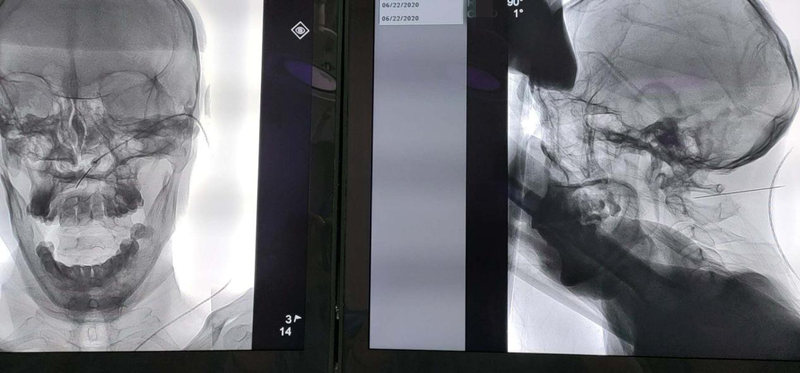

原来,1个月前,卞叔叔无明显诱因出现头枕区疼痛,夜间疼痛明显,严重影响睡眠,3天后疼痛部位出现疱疹。在当地医院就诊,经药物治疗一周后,疱疹就消失了,可是疼痛非但没有减轻,却有越来越重的趋势。先后又去了多家医院就诊,疼痛都没有改善,自己也失却了信心。卞叔叔说,因头枕区疱疹后疼痛已经1个月没睡好觉了。就在几天前,卞叔叔到上海一家医院体检时,他想,这家全国知名的大医院,一定有办法解决他的疼痛,不料想,医生却推荐他到 疼痛科找张赢主任治疗。卞叔叔没有犹豫,相信上海的专家都推荐的,准没错!当天连夜驾车从上海就来到苏州住下了。次日一上班,就来到了张主任门诊。张赢主任详细询问了病史后,给出了治疗方案,他毫不犹豫地接受了住院治疗。

入院当天,管床医生联系各个辅助科室帮助他尽早完善辅助检查,为手术做积极准备。第三天,张赢主任为卞叔叔顺利地完成了脉冲射频的颈神经节调理术。医生没有辜负卞叔叔的期望,一下手术台,他就说兴奋地说,疼痛减轻了一大半。已经一个多月没有睡过好觉的卞叔叔,第二天一早逢人就说:“昨晚睡得好香啊”。三天后,经过第二次射频调理,卞叔叔的疼痛完全消失了。他说,如果早知道这里能看好我的病,早就来了!经过10天的系统治疗,他开心地出院了。出院那天一大早,就将三面锦旗送至疼痛科医护团队的手里,还激动地说,送一面锦旗,不足以表达对疼痛科全体医护人员的感激之情,必须送三面。